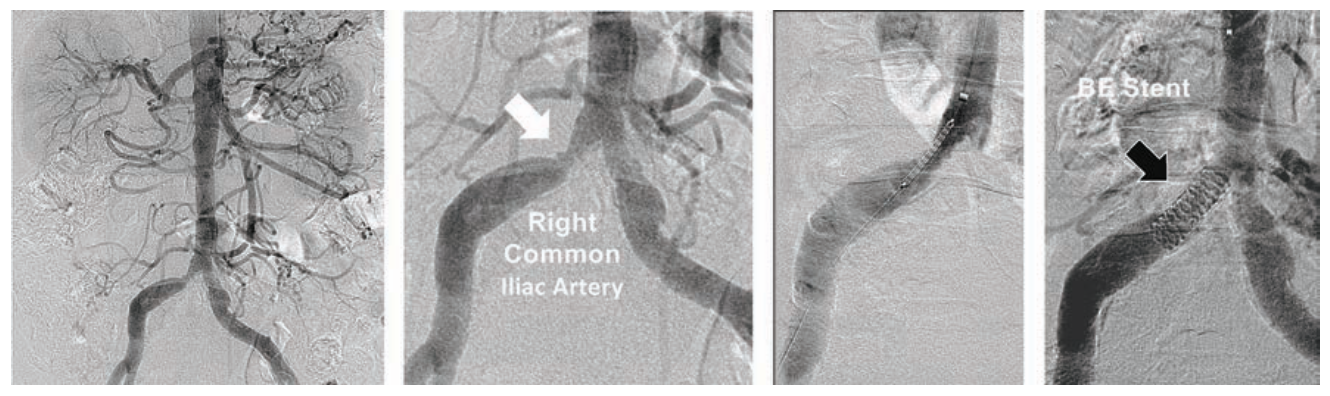

Case #3

A 78-year-old short and obese Hispanic female (4 feet 10 inches, 147 centimeters in height, weight 200 pounds/90.7 kg) was referred with severe bilateral leg claudication, with critical limb ischemia due to a non-healing left foot wound. Using 5 Fr right TRA, abdominal aortography identified a right common iliac stenosis (Figure 3A). A 150 cm TrailBlazer catheter was advanced over a 300 cm Wholey guidewire into both common femoral arteries, and angiography revealed a short chronic total occlusion (CTO) of the left SFA, significant right SFA disease (Figure 3B), with 2-vessel tibial runoff into intact pedal arches bilaterally. The TrailBlazer catheter was further advanced over the Wholey guidewire to a level just above each SFA lesion, to confirm that the distance from right TRA to target lesions did not exceed 150 cm, the length of the device technology catheters being considered for therapy. In the right leg, following injection of 500 mcg of nitroglycerin through the TrailBlazer catheter, a significant 60 mmHg trans-stenotic pressure gradient was measured across the right iliac artery stenosis.

Using the Wholey guidewire, a 90 cm 5 Fr Flexor Shuttle sheath was first advanced into the left external iliac artery. The TrailBlazer catheter was positioned immediately above the left SFA CTO, and connected to a manifold using a Tuohy-Borst adapter (Cook Medical). This allowed injections of 2-4 cc of contrast for facilitating chronic total occlusion (CTO) crossing with a .014-inch 300 cm long Grand Slam (Abbott Vascular) coronary guidewire. Treatment was performed with an .018-inch Armada PTA balloon 6 mm x 60 mm on a 150 cm catheter (Abbott). A 5 Fr-compatible .035-inch EverFlex with Entrust delivery system self-expanding (SE) 7 mm x 80 mm stent on a 150 cm catheter (Medtronic) was deployed in the left SFA, then post-dilated with the Armada 6 mm x 60 mm balloon (Figure 3B). The Flexor Shuttle sheath was redirected using the Wholey guidewire into the right external iliac artery, with exchange for the .014-inch 300 cm guidewire. The right SFA was treated with overlapping EverFlex Entrust SE stents measuring 6 mm x 60 mm and 6 mm x 40 mm, with post-dilatation using an Armada 5 mm x 60 mm balloon (Figure 3B). Pre-dilation of the right common iliac artery stenosis was performed with a .014-inch Viatrac 14 Plus RX 7 mm x 15 mm PTA balloon (Abbott), followed by a .014-inch Herculink Elite RX 7 mm x 18 mm balloon-expandable (BE) stent (Abbott), both on 135 cm monorail catheters (Figure 3A). The patient was discharged 3 hours later following use of a TR Band. Her left foot wound healed within one month, her claudication resolved, and ABIs remained normal at two-year follow-up.

Tips and Tricks for 5 Fr Stenting in the SFA and Iliac Artery

This case predated the availability of the 018 IN.PACT DCB on a 200-cm long catheter. The 150 cm Trailblazer catheter has three marker bands embedded in the distal end, spaced apart by 50 mm. This catheter was used to measure the “intravascular distance” from the hub of the radial access sheath to the SFA target lesions, and verified that PTA balloons and the EverFlex Entrust SE stents on 150 cm catheters could reach the SFA disease. By using a Tuohy-Borst adapter, the TrailBlazer support catheter was converted to a “mini guide” catheter, allowing contrast injections of 2-4 cc to facilitate crossing the left SFA CTO and right SFA disease with an .014-inch guidewire. The Viatrac 14 RX PTA balloon and the Herculink Elite RX BE stent allowed single operator guidewire control for catheter advancement and retrieval from the common iliac artery. The Viatrac and Herculink RX device technologies are both currently available in up to 7 mm diameters for 5 Fr sheath size. At present, treatment with PTA and BE stents in 8 mm diameters or greater requires exchange for a 6 Fr radial access sheath to accommodate the larger diameter over-the-wire catheters.